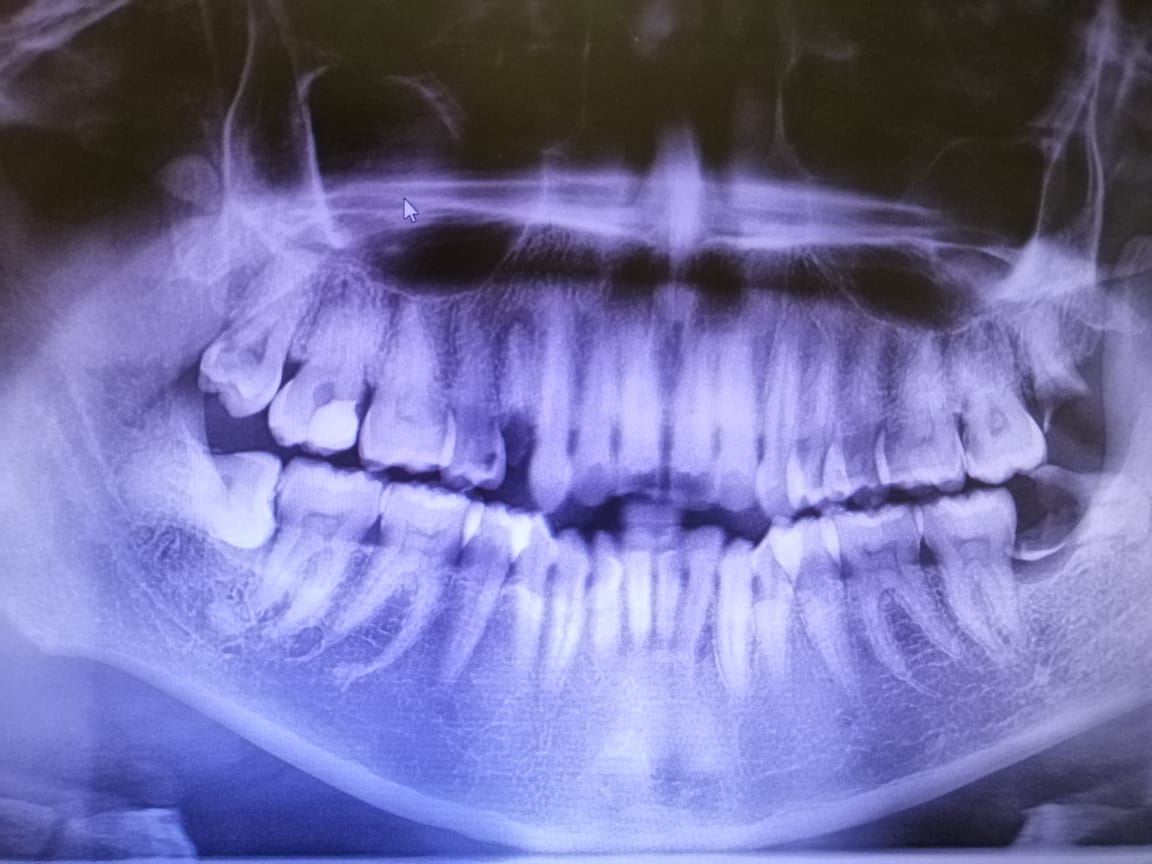

基本上牙医做的治疗来来去去也是那几样。补牙filling, 绑牙braces, 拔牙extraction, 洗牙scaling,做牙冠crowning, 根管治疗root canal treatment。

偶尔会有植牙implant 和 口腔小手术minor oral surgery ,也就是我比较喜欢的因为可以看到gum被切开,过程比较复杂,可是我觉得很好玩,很有挑战性!病人才是最大的挑战!